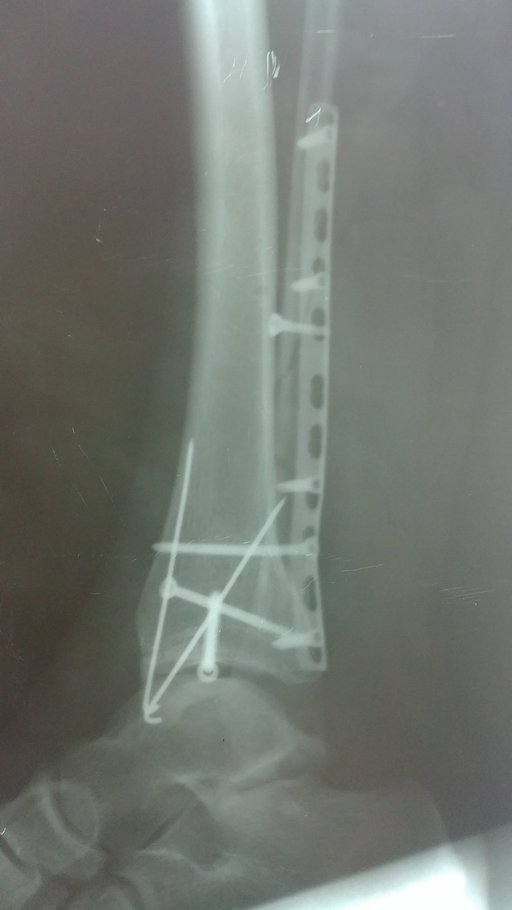

Хвора О. звернулася в травмпункт КНП ТМКЛШД через 5 години після травми яку отримала в побуті при падінні зі стільця. Оглянута травматологом травмпункту, направлена на рентгенографію. Згідно даних рентгенограм встановлено діагноз: Закритий перелом обох кісточок правої гомілки та заднього краю в\гомілкової кістки зі зміщенням уламків. Розрив ДМГС справа. Хворій накладено тимчасову фіксацію та направлено в приймальне відділення КНП ТМКЛШД. Хвора повторно оглянута травматологом стаціонару. При огляді відмічається виражений набряк, біль, порушення функції н\кінцівки. Встановлено діагноз : Закритий перелом обох кісточок правої гомілки та заднього краю в\гомілкової кістки зі зміщенням уламків. Розрив ДМГС зліва. Оскільки на момент огляду у хворої відмічався незадовільний стан м’яких тканин хворій було запропоновано проміжне оперативне втручання з фіксацією г\ступневого суглобу в АЗФ або проміжне лікування системою скелетного витяжіння. При госпіталізації проведено необхідні інструментальні та лабораторні методи обстежень. Хвора відмовилася від накладання АЗФ. Вибрано метод лікування скелетним витягом. Під час перебування у відділенні хвора отримувала протинабрякову терапію, знеболюючі препарати, антикоагулянти. На 8-му добу лікування скелетним витягом набряк спав, м’які тканини перебували в задовільному стані. Хворій проведено демонтаж ССК. Та проведено оперативне втручання: Відкрита репозиція з МОС перелому зовнішньої кісточки пластиною LCP та відкрита репозиція з МОС внутрішньої кісточки спицею та гвинтом. Фіксація ДМГС позиційним гвинтом. Після оперативного втручання хвора переведена в палату. З 2-3 доби хворій дозволено активні рухи у г\ступневому суглобі без навантаження на праву н\кінцівку. Шви знято на 12 добу, хвора в задовільному стані з наданими рекомендаціями щодо тактики подальшого лікування та реабілітації виписана з травматологічного відділення.